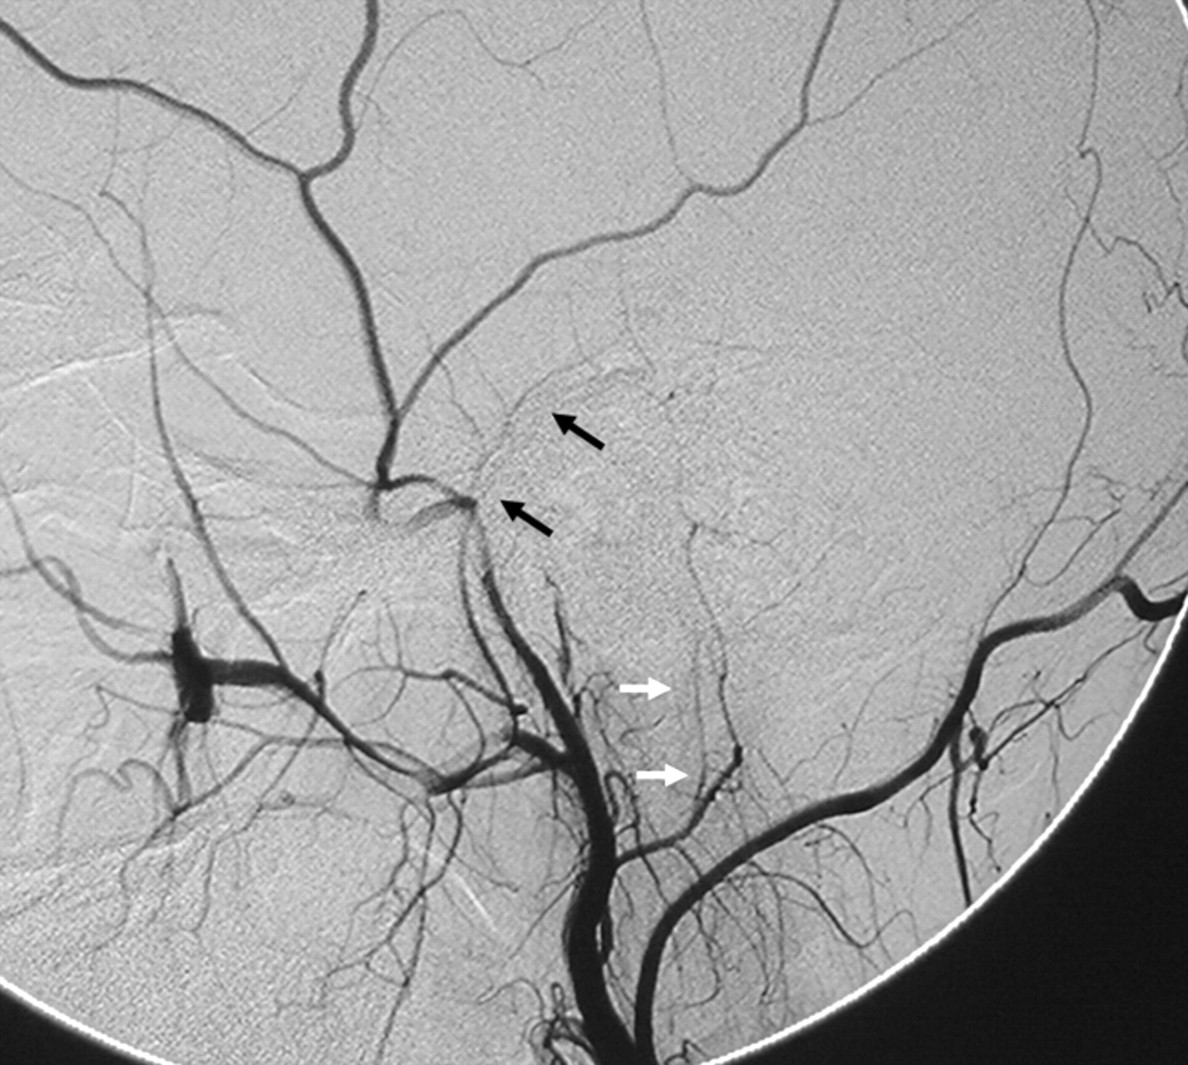

As a remnant of the embryologic hypoglossal artery, the ascending pharyngeal artery keeps its connection with the vertebral artery through 2 proximal branches.7,36,37 The lowest, usually the most proximal branch of the ascending pharyngeal artery, is the musculospinal branch, which anastomoses laterally with the C3 radicular anastomotic artery of the vertebral artery (Fig 12). The second is the prevertebral branch, located on the ventral surface of the C1–C2 vertebrae and anastomoses with the odontoid arch.38,39 This branch typically arises from the neuromeningeal trunk but may also arise directly from the main ascending pharyngeal artery. It has a characteristic U-shaped curve, seen on the lateral view before anastomosing medially on the surface of the dens with the C3 collaterals from the vertebral artery (Figs 12 and 13).

Right ascending pharyngeal artery (A) and left vertebral artery (C) angiograms in the anteroposterior view and left ascending pharyngeal artery angiogram in the lateral view (B) show the anastomosis around the odontoid arch (arrowheads) with branches from the neuromeningeal trunks (black arrows) and the C3 segment of the left vertebral artery (white arrows).